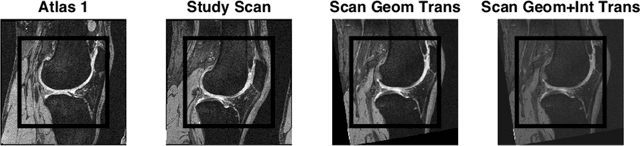

Abstract:Scanner drift is a well-known magnetic resonance imaging (MRI) artifact characterized by gradual signal degradation and scan intensity changes over time. In addition, hardware and software updates may imply abrupt changes in signal. The combined effects are particularly challenging for automatic image analysis methods used in longitudinal studies. The implication is increased measurement variation and a risk of bias in the estimations (e.g. in the volume change for a structure). We proposed two quite different approaches for scanner drift normalization and demonstrated the performance for segmentation of knee MRI using the fully automatic KneeIQ framework. The validation included a total of 1975 scans from both high-field and low-field MRI. The results demonstrated that the pre-processing method denoted Atlas Affine Normalization significantly removed scanner drift effects and ensured that the cartilage volume change quantifications became consistent with manual expert scores.